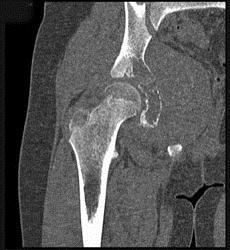

问题 男,15岁,右髋部疼痛、红肿,有压痛,皮温增高,结合图像,最可能的诊断是 ( )

选项 A、转移性神经母细胞瘤 B、骨结核 C、急性骨髓炎 D、Ewing肉瘤 E、骨肉瘤

答案 D